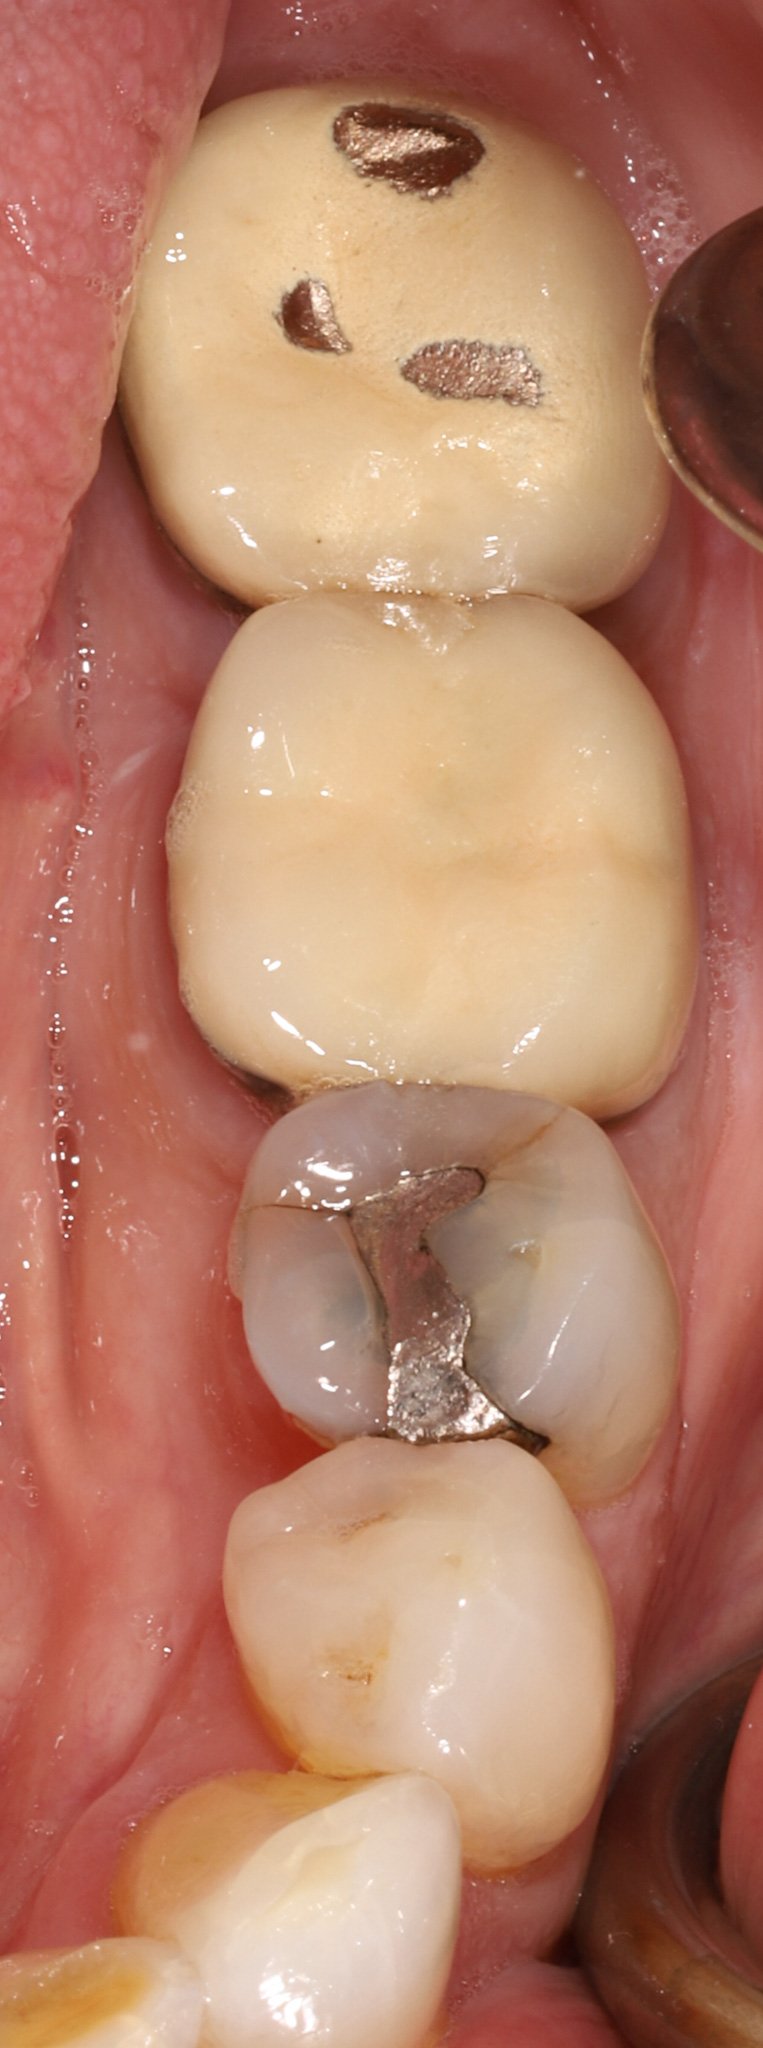

Close-up of a person's molar teeth with leakage, cracks and decay.  Prior to restorative treatment.

Before: Large silver fillings with leakage and cracks

Close-up of a person's molar teeth restored with gold and composite resin.

After: Gold partial coverage restoration to protect from further fracture